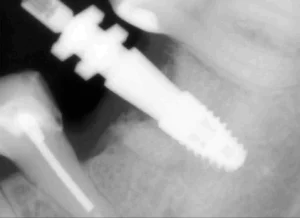

- Высокоточная установка импланта. Процесс установки импланта Штрауман выполняется с применением современных хирургических методов, обеспечивающих точность, минимальную травматичность и высокую эффективность процедуры.